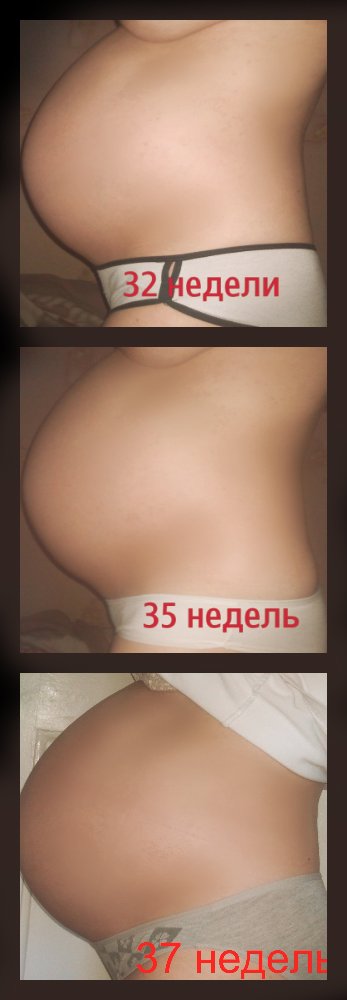

Тошнота на 37 неделе беременности: причины и рекомендации